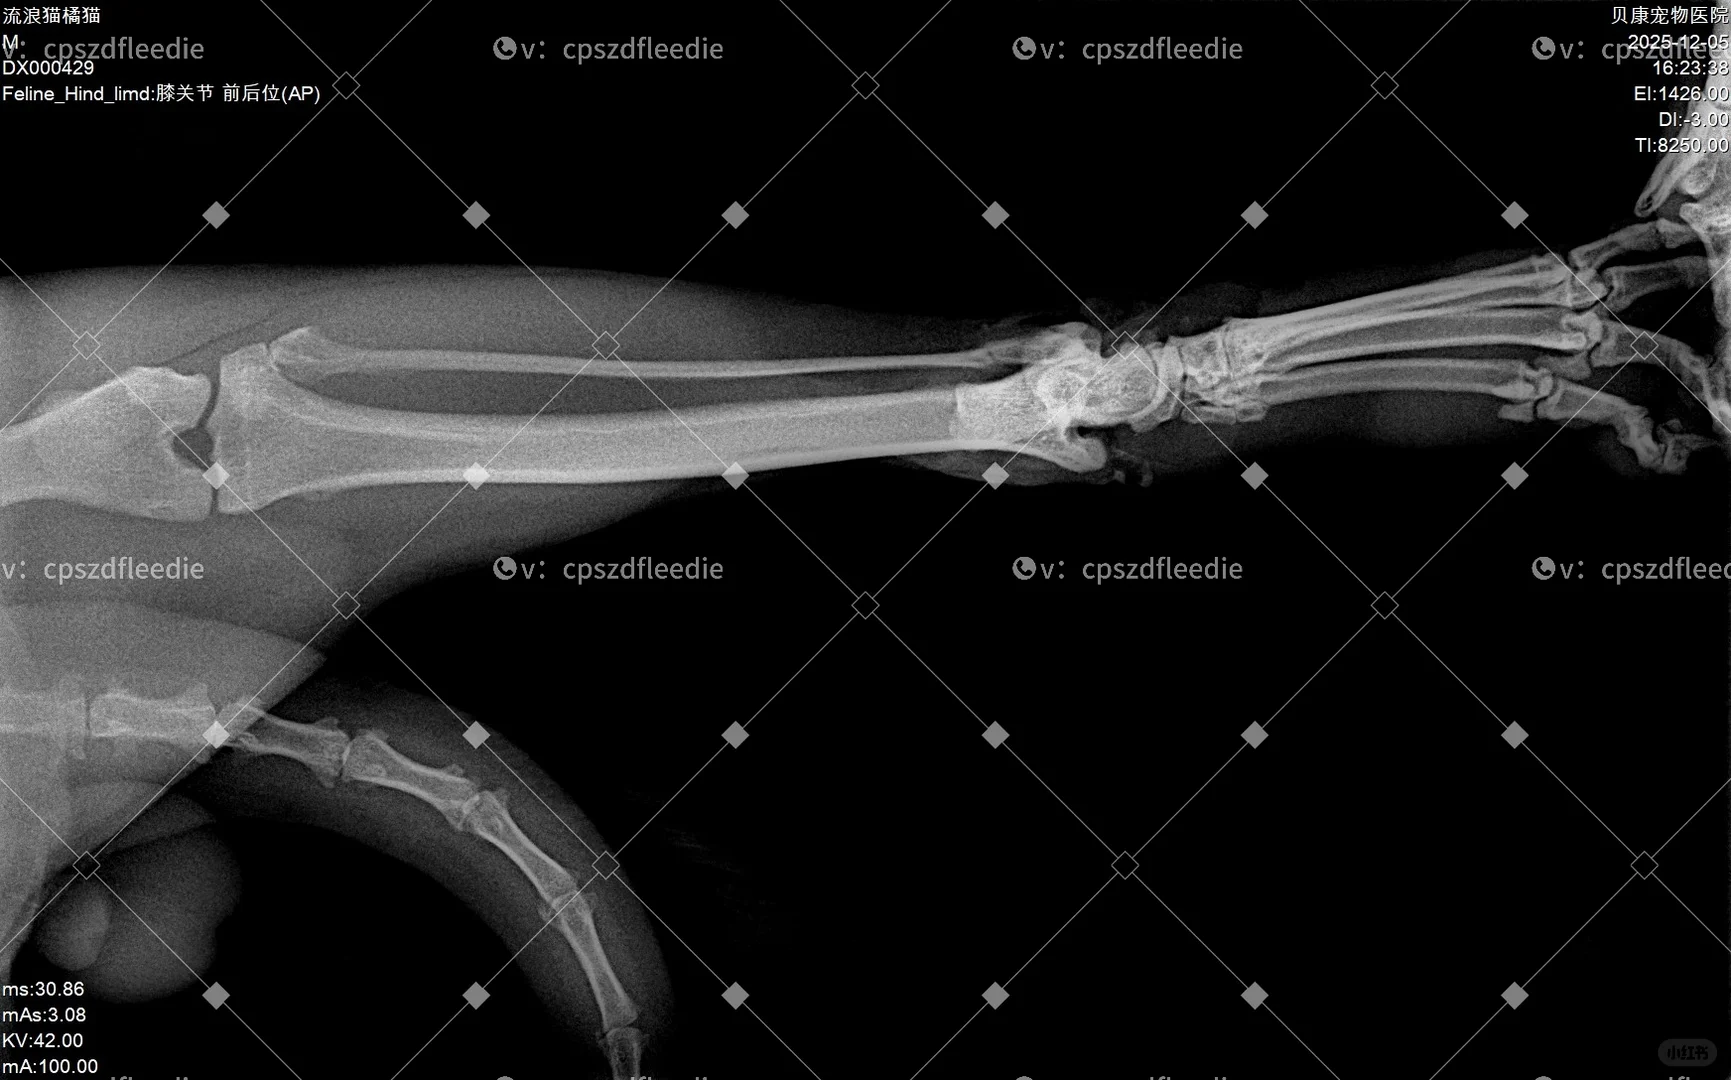

目前情况:一条后腿骨折+神经断了两根,尾巴尖部截肢,先付了外伤处理+住院一周的费用770r。医生说目前不建议做骨折手术,原因是骨折部位离关节很近,并且外伤面积过大,非常容易感染,肉里面都是灰尘。